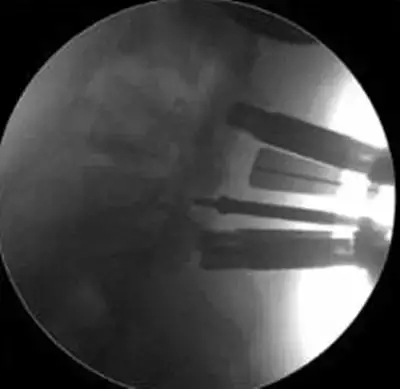

劉志安副院長(zhǎng)所說的“微創(chuàng)小切口”就是通道下髓核摘除植骨融合經(jīng)皮內(nèi)固定術(shù)。其原理就是利用MIS-TLIF技術(shù)微創(chuàng)治療腰椎疾病,不但能達(dá)到開放手術(shù)的效果,且切口及創(chuàng)傷為開放切口的1/3,術(shù)中出血量少,患者術(shù)后可以恢復(fù)更快。

據(jù)劉院長(zhǎng)介紹,MIS-TLIF技術(shù)是經(jīng)椎旁肌間隙入路運(yùn)用脊柱內(nèi)鏡或?qū)S猛ǖ佬醒甸g盤切除、椎管減壓、植骨內(nèi)固定術(shù),是一項(xiàng)應(yīng)用廣泛、技術(shù)成熟的脊柱微創(chuàng)手術(shù)方法。本技術(shù)可以完成與傳統(tǒng)手術(shù)完全相同的椎間盤切除、椎間植骨融合內(nèi)固定等操作。手術(shù)切口一般3-5厘米,本手術(shù)方式可有效避免傳統(tǒng)手術(shù)對(duì)腰背肌肉的損傷,患者術(shù)后腰背部疼痛輕、恢復(fù)快,手術(shù)效果優(yōu)于傳統(tǒng)手術(shù),治療后1-3天即可下床活動(dòng)。本技術(shù)適于大部分的腰椎間盤突出癥、腰椎管狹窄癥、腰椎滑脫癥等。